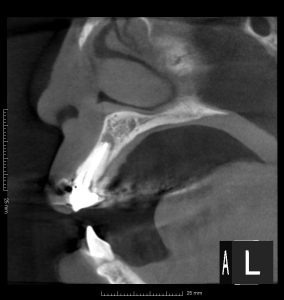

レントゲンを見てみよう。

(術前のレントゲン、CT)

右上2、左上1、左上2に根尖病変がある。

また、左右2番の根尖部に圧痛を認めた。

過去の根管治療ではラバーダムは使用していなかったとのこと。

4本の根管治療のうち、3本が失敗し、根尖病変ができている。